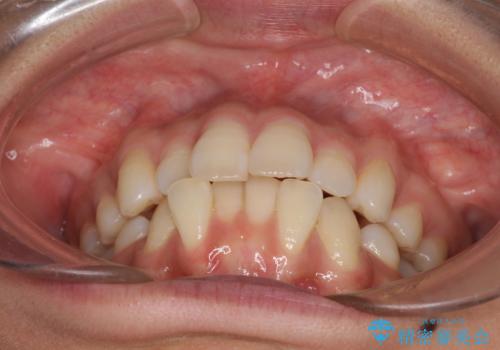

- 以前の矯正治療の後戻りにより、上下の前歯がでこぼこになってしまったことを気にして来院された患者様です。

口元がこれ以上突出することなく前歯の叢生が改善できるよう、歯と歯の間を削ってスペースを獲得し、インビザラインを用いて整えていくこととしました。

目安の装着時間である1日22時間をしっかりと実践してくださり、半年強という短期間で治療を終えることができました。